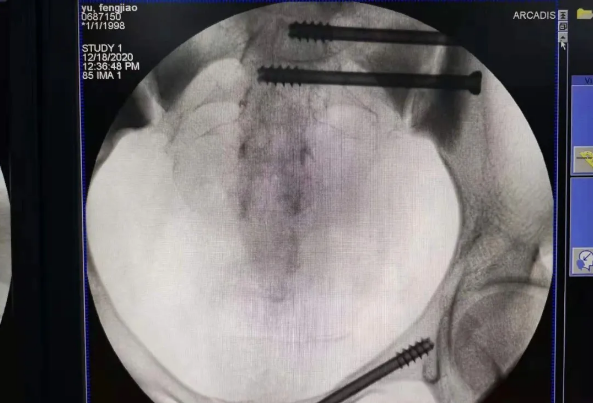

在南昌市第一醫院廖琦教授帶領下,由創傷骨科團隊借助天璣?骨科手術機器人為患者“量身定做”最理想、最安全的教科書般的通道,完美安全微創完成手術,并且手術時間明顯縮短,真正做到“指哪兒打哪兒”!更讓患者放心的是,天璣?骨科手術機器人的“穩定手”機械臂進行精準定位,不用反復探尋。

天璣?骨科手術機器人系統由機械臂主機、光學跟蹤系統、主控臺車構成,“透視眼”、“穩定手”是它的厲害之處,因此一舉解決了骨科手術有三大難題:視野差、精準難、不穩定。

? 機械臂就是天璣?骨科手術機器人的“穩定手”,運動靈活、操作穩定,能達到亞毫米的精度;

? 主控電腦系統就等于天璣?骨科手術機器人的大腦,智能傳達著醫生的想法給以上兩個設備,幫助醫生進行“路徑規劃”,術中還能跟蹤患者術中的移動,機器人手臂位置自動補償,保障手術路徑與計劃路徑一致。